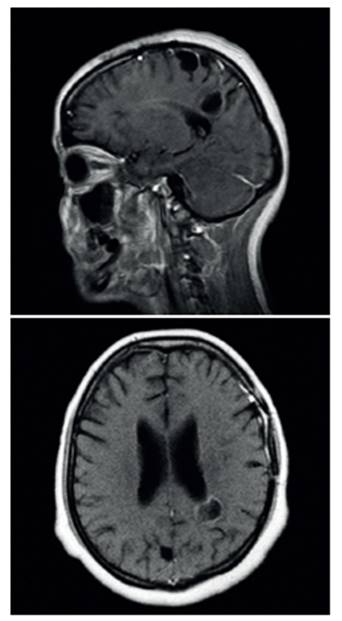

Cuatro meses después de la alta hospitalaria, la paciente refirió persistencia de cefalea, por lo cual se valoró en el servicio de consulta externa con RMN de control. En aquel estudio, se evidenció falta de respuesta de las lesiones descritas antes del manejo antiparasitario, con lesiones quísticas parietales con tendencia a la progresión (Figura 2). Por lo anterior, se planteó la posibilidad de estar frente a un caso de NCC resistente a manejo antihelmíntico o ineficacia propia del albendazol genérico, administrado durante el primer ciclo terapéutico.

Figura 2 RMN contrastada proyección sagital y axial, donde se evidencia progresión de las lesiones quísticas múltiples y resolución de quiste frontoparietal izquierdo.